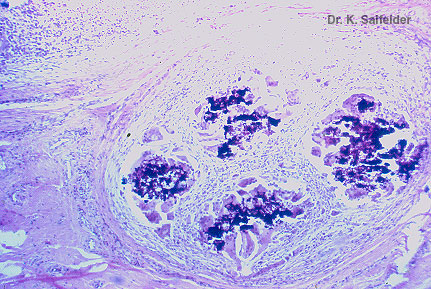

Abb. 16,41: Myzetome

Eumyzetom. Mehrere Drusen von Leptosphaera senegalensis. HE-Faerbung